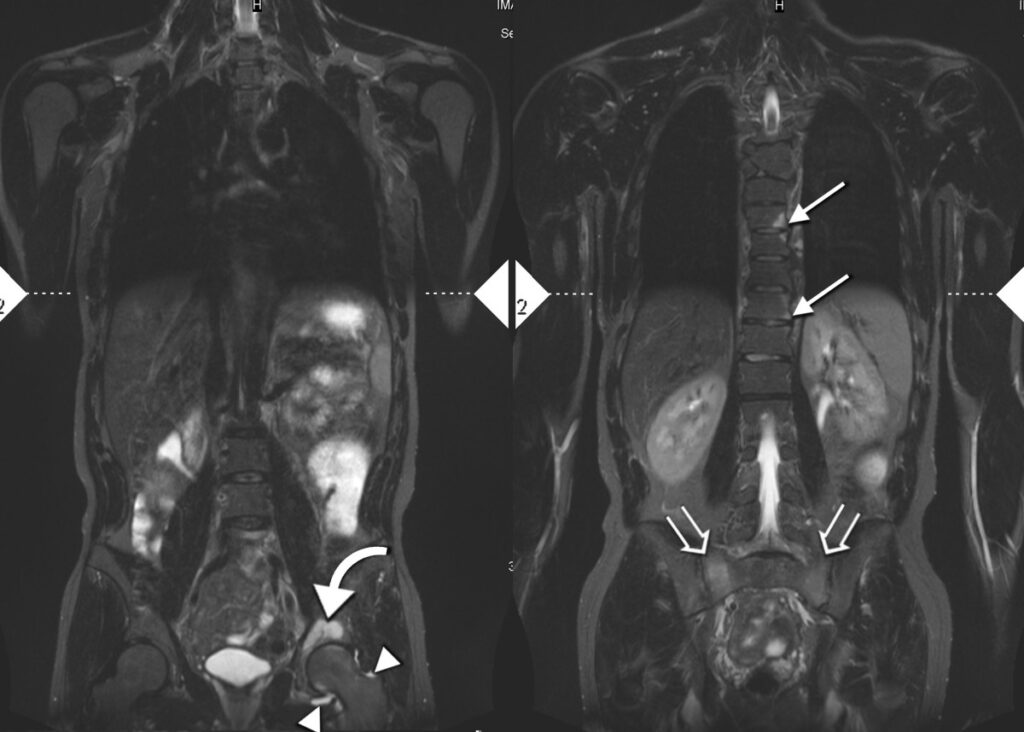

Při diagnostice nemoci se přihlíží i k rentgenovým snímkům a krevním testům. Bohužel ale některé časné formy onemocnění nejsou na rentgenu rozpoznatelné, a přesná diagnóza se tak oddaluje.